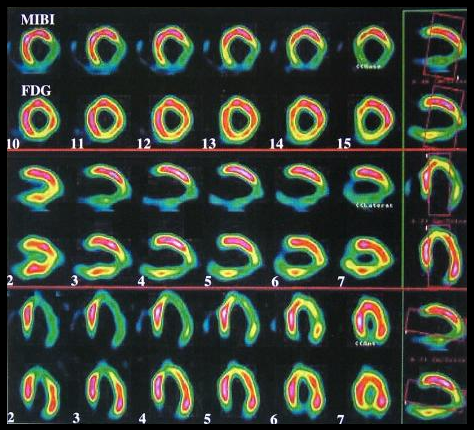

心血管系统:PET/CT可以与SPECT心肌血流灌注显像(MPI)联合应用,99mTcMIBI灌注显像提示下后壁、外侧壁、心尖部放射性分布稀疏缺损;F-FDG PET代谢显像与之不匹配,下后壁、外侧壁、心尖部FDG有明显摄取。提示以存活心肌为主。